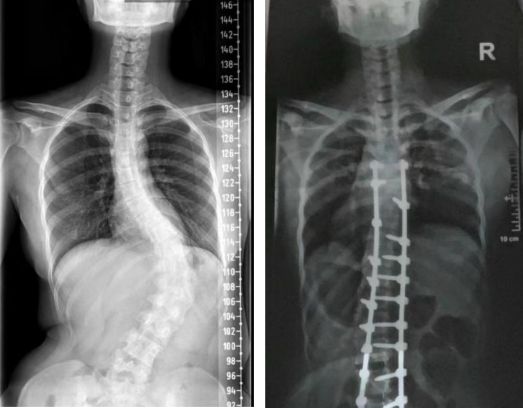

陈默在2023年8月进行了手术。她的手术一切顺利。术后,她长高了4厘米,背部基本平了,原本一侧外翻的肋骨也变得对称了。两个月后她能起来走走了,看着外面的天空,她忽然觉得天很蓝,云很白,风很轻柔,自己回到了很久以前,那个没有生病的小时候。

左为术前X光片,右为术后X光片,图源受访者